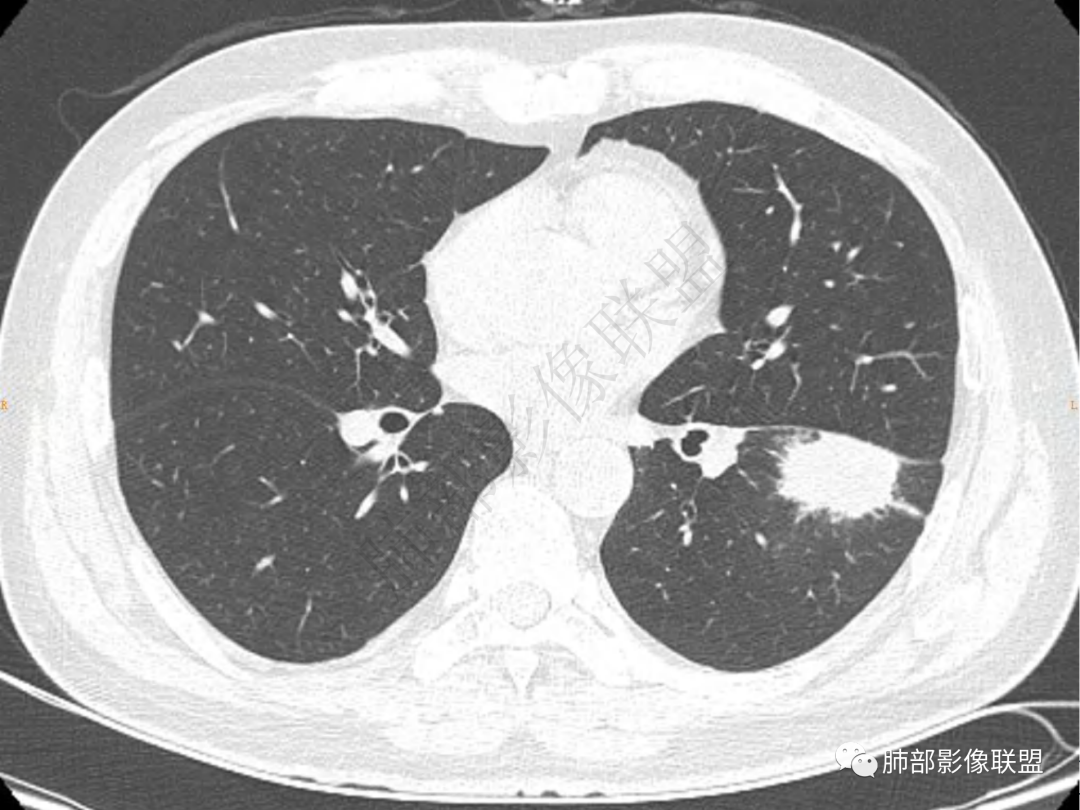

1.中年男性,咳嗽咳痰20余天,间断咯血2周

2.左肺下叶团片影,跨背段及内前基底段,实性部分类椭圆形,密度不甚均匀,可见毛刺及棘状突起,未见典型分叶及胸膜凹陷。病灶上下缘可见相应肺段支气管旁进侧出,管壁轻度增厚,未见狭窄阻塞。

3.周边较大范围磨玻璃影,边界相当模糊,小叶增厚明显。注意叶裂另一侧、左肺舌段亦可见磨玻璃影及增厚的小叶间隔。未见明确卫星病灶。

1.病灶不够密实,没有典型分叶,收缩乏力等,支气管未见截断等,缺乏一般肿瘤性肿块特征。

2.周围磨玻璃影边界不清缺乏限制,甚至“激惹”到相邻肺叶,也许提示较明显的炎性水肿。

正如多数老师分析到的,本例病灶炎性特点比较明显。